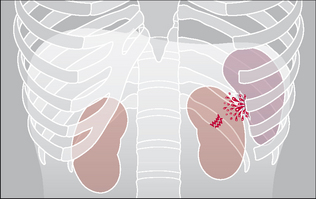

Figure 32.14 Blunt trauma. Lung contusion. Various appearances may result: an area of consolidation (right lung); or cavitation; or a cystic area, i.e. a pneumatocoele (left lung).